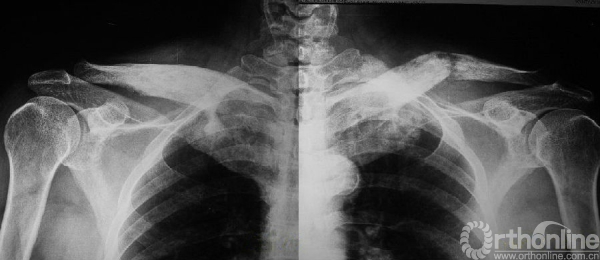

(2)多发型:占骨纤维异样增殖症的30%,病变可侵犯全身多数骨骼,常偏于一侧肢体骨,常以中线为界,严重的可造成肢体短缩(图3),偶尔也有双侧生长(图4)。

图4 左右锁骨同时发病,左侧并病理性骨折